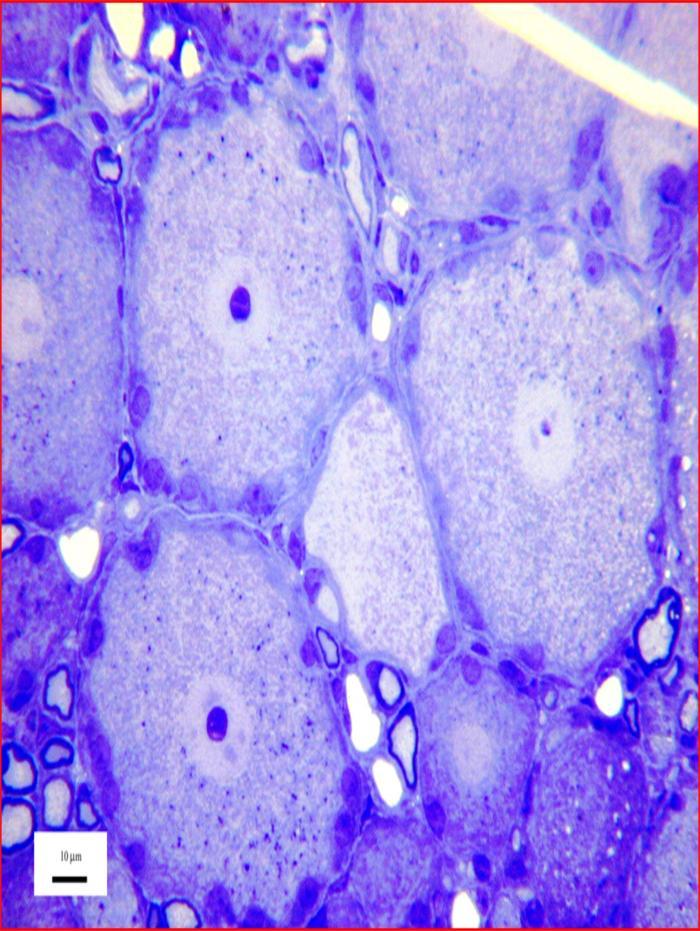

Image above: Microscopy image of Sensory nerve cells, courtesy of Dr R W Banks.

Sensory nerve cells such as these are located in a swelling, or ganglion, on the dorsal root of a nerve connected to the spinal cord. Each gives rise to a single nerve fibre, or axon, that branches once within the ganglion. One branch enters the spinal cord to make connexions with other nerve cells, while the other passes through peripheral nerves to form a sensory ending in skin, muscle, joints, viscera, etc. The endings are usually specialised to respond variously to touch, pressure, movement, heat, etc. The tissue has been chemically fixed, dehydrated, and embedded in epoxy resin. The section was cut with a glass knife and is 1 micrometre thick. It was stained with toluidine blue for light microscopy.